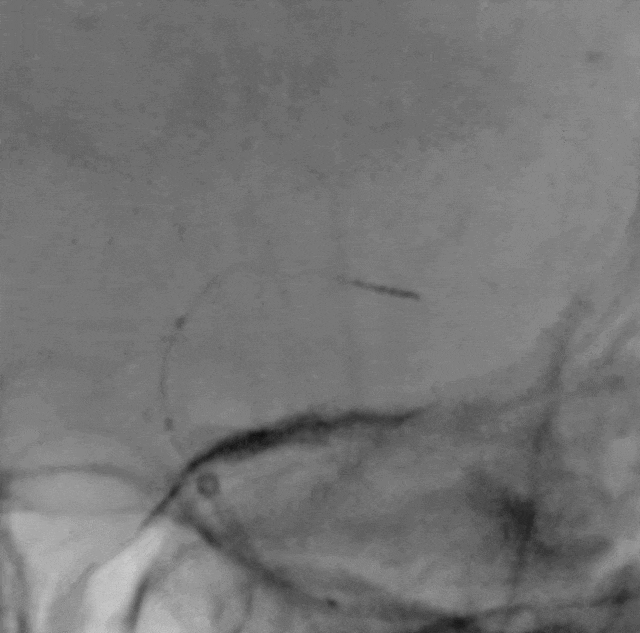

Catalyst 6 中间导管在5.5F Introsky X导管鞘内输送顺利,微导丝、微导管超选越过闭塞段。

什么叫桡鞘【例久弥新】寻道于桡——瑞康通5.5F Introsky X导管鞘经桡取栓一例_https://www.jmylbn.com_新闻资讯_第17张

什么叫桡鞘【例久弥新】寻道于桡——瑞康通5.5F Introsky X导管鞘经桡取栓一例_https://www.jmylbn.com_新闻资讯_第18张

什么叫桡鞘【例久弥新】寻道于桡——瑞康通5.5F Introsky X导管鞘经桡取栓一例_https://www.jmylbn.com_新闻资讯_第19张